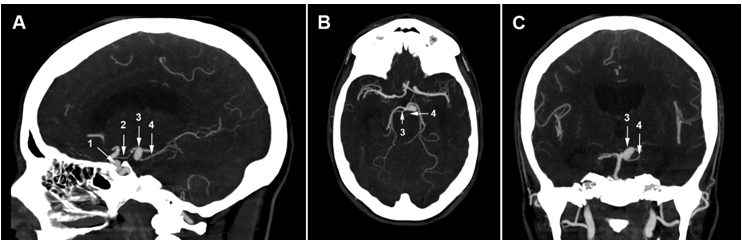

A 43-year-old hypertensive woman visited the emergency department of her local community for a sudden onset of headaches. On the physical exam, she was hemodynamically stable with a blood pressure of 150/90 mm Hg. Her Glasgow Coma Scale (GCS) score was 15/15, and her pupils were isochoric and reactive to light and accommodation. No seizures, visual disturbance, sensorimotor deficit, or fever were noticed. A brain CT showed diffuse SAH with blood in basal cisterns, cerebellar tentorium, and temporal sulci associated with discreet brain edema (Figure 1). The SAH was graded as Hunt and Hess grade 1 and Fisher CT grade 3. Given brain CT results and hypertensive peak, aneurysmal SAH was suspected. Thus, the patient was referred to the neurosurgery department. On admission, her GCS score was 14/15, and she had neck stiffness, photophobia, and phonophobia. In addition, left-sided ptosis and mydriasis were elicited, suggesting left oculomotor nerve palsy. The DSA was unavailable at our institution (a public hospital), and the cost was prohibitive at private facilities. So, a brain CTA with 3D reconstruction was performed, which revealed a 10 mm left paraclinoid aneurysm and a 9 mm left PCA aneurysm (Figure 2, Figure 3, Figure 4). The initial therapeutic strategy was maintaining systolic pressure between 120 and 140 mm Hg using an antihypertensive drug and preventing vasospasm using nimodipine. Since endovascular therapy was unavailable, surgeons chose surgical clipping. Therefore, the patient was transferred to the operating room, placed in the dorsal decubitus position, and the head right turned 60 degrees. Then, a left fronto-temporo-pterional craniotomy was performed. The paraclinoid aneurysm was oriented behind and was wide-necked. Its sac was bilobed and close to the pituitary fossa, the posterior communicating artery (PCOA), the superior wall of the cavernous sinus, and the left clinoid processes. Thus, the operating field was too narrow, and clipping might injure surrounding structures. Therefore, surgeons preferred muscle wrapping instead of clipping. The posterior aneurysm had a wide neck involving the left SCA and PCA origins and was close to the P1 and P2 segments. However, there was a good safety margin to clip the neck without interrupting the blood flow in the SCA and the PCA, which has been done. Despite successful surgery, the patient remained unconscious. On the sixth postoperative day, a brain CT was performed. It revealed a ventricular hemorrhage with diffuse cerebral edema, graded as Hunt and Hess 5 and Fisher CT grade 4. Thus, an external ventricular drain was urgently placed. Unfortunately, the patient succumbed to this event.

Figure 1.Brain CT scan slices: white arrows indicate the subarachnoid hemorrhage in basal cisterns, cerebellar tentorium, and temporal sulci.